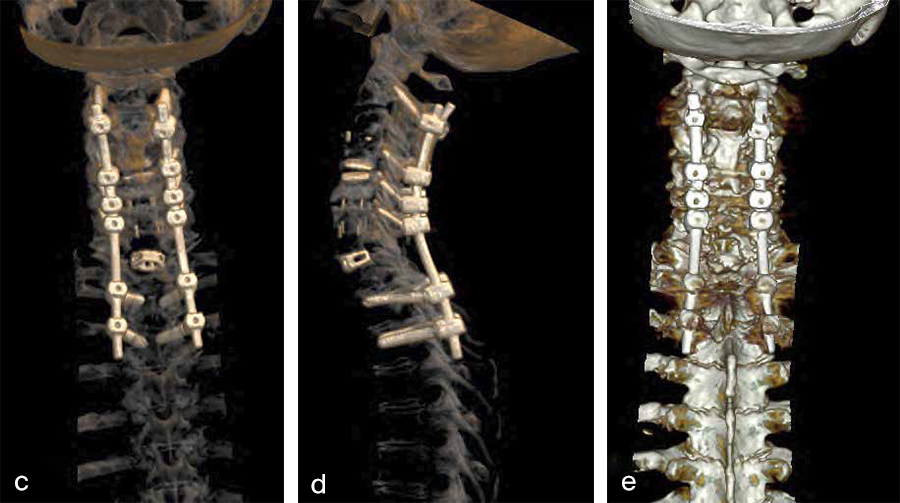

Second, a posterior revision surgery was performed including implant removal of the posterior instrumentation between C2 and C4 followed by a laminectomy of C7 with bilateral foraminotomy of the C8 nerve routes. Re-instrumentation with isthmic screws at the level C2, lateral mass screws at the level C4, C5, and C6, as well as bilateral pedicle screws at the level T2 and T3 were performed using the new Symphony system (DPS). The Symphony system offered the opportunity to place 4.0 mm screws in the previous loosened screw location at the level C2. The 3.5 mm screws were placed in C4, C5, and C6, and 5.5 and 5.0 mm screws at T2 and T3, respectively. The 4.0 mm rod allowed a good direct connection between the cervical spine isthmic and lateral mass screws and the thoracic pedicle screws, providing adequate stability and allowing excellent reduction. An intraoperative image is shown in Fig 3. Postoperative radiographic evaluations are displayed in Fig 4.